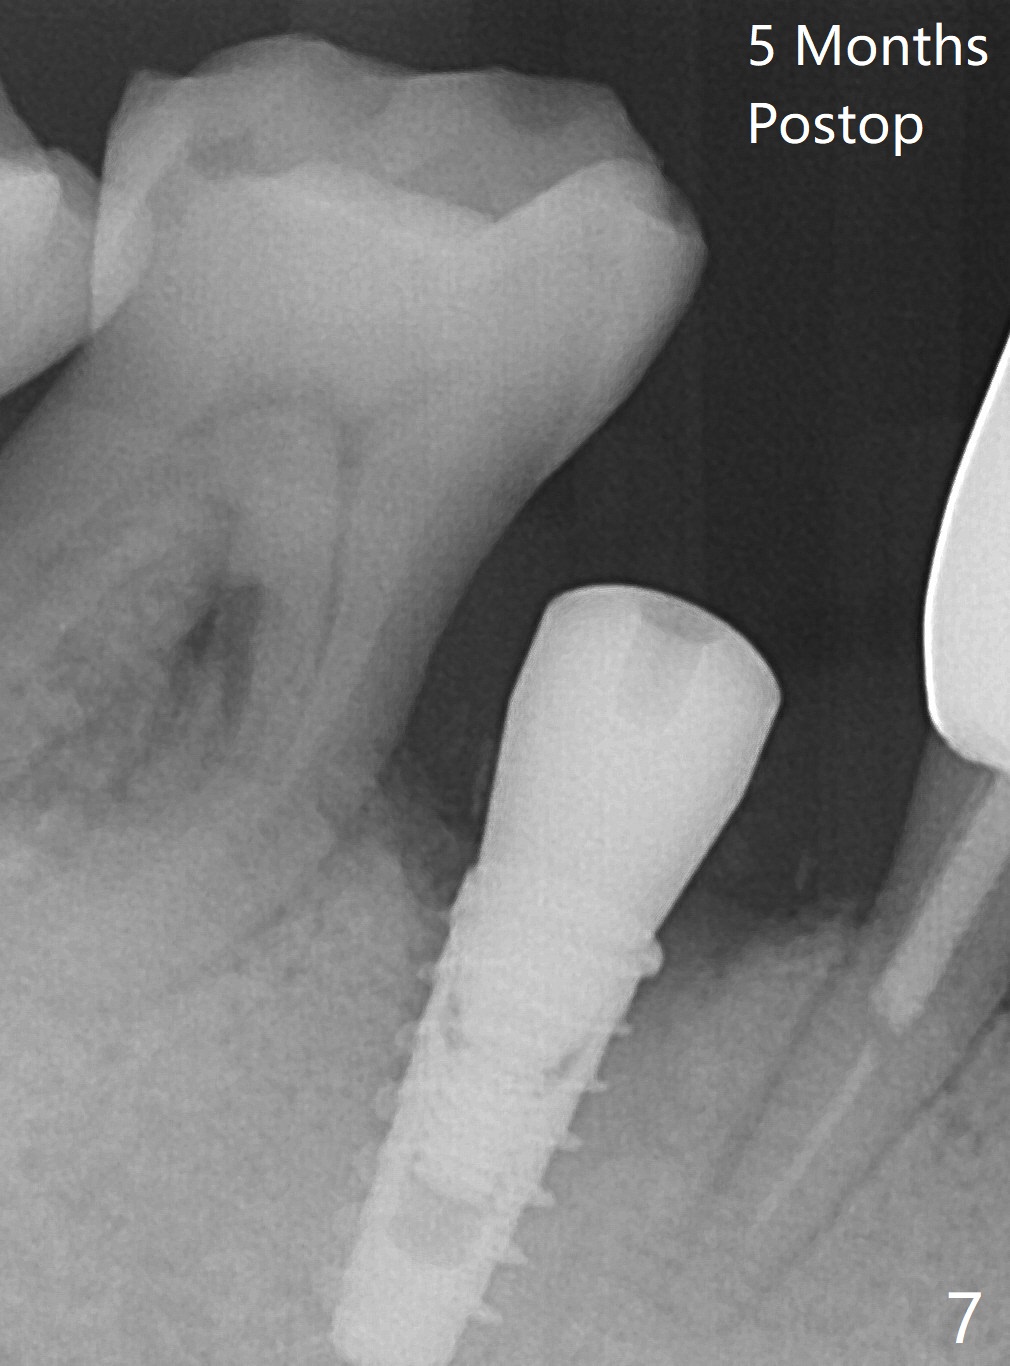

The tooth #29 is easily extracted with granulation tissue attached to the apex (Fig.1,2). The buccal plate is low. Initial osteotomy is established in the mesial slope of the socket for 13 mm subgingival (Fig.3 red dashed line). After adjustment of the osteotomy position and use of Magic Drills 2.8 and 3.3 mm for 15 mm subgingival, a 4x9 mm dummy implant is placed 2 mm subgingival (Fig.4). Final implant (Fig.5: 4x9 mm; red dashed line: socket) is placed 4 mm subgingival (supracrestal buccal; infracrestal lingual); Vanilla graft placed buccodistal (*). With placement of a 4.5x5.7(4) mm abutment (Fig.5), an infraocclusal immediate provisional (Fig.6 P) is fabricated to maintain the interdental papillae. One month later, the abutment dislodges. The patient insists upon no provisional so that he can masticate on the right side, since there is no functional molars on the left side. The implant appears to have osteointegrated 5 months postop (Fig7). The crown is loose 2.5 months post cementation (8.5 months postop); there is bone loss around the implant (Fig.8 *). Vanilla graft is placed after implant removal (Fig.9); in fact the neighboring teeth also have mobility (including periapical radiolucency at #30 (Fig.9 *)).